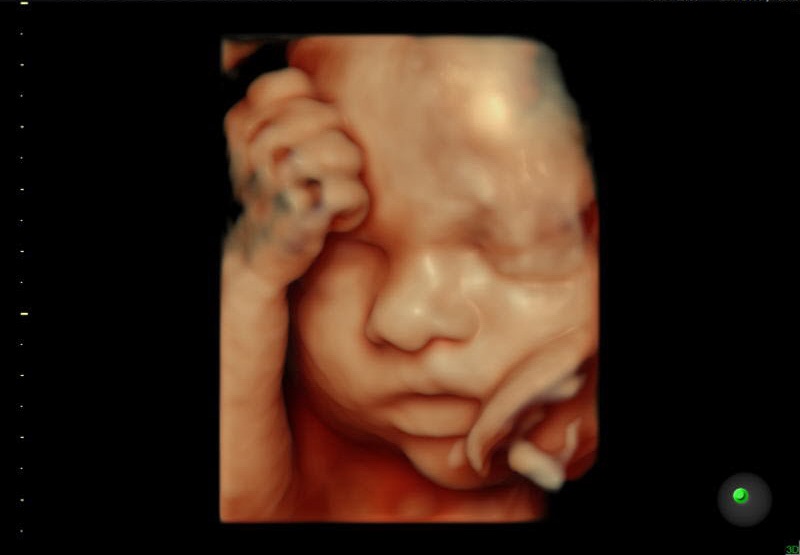

Ecografía de un bebé en el vientre materno.

Sobre la interrupción voluntaria del embarazo, ha escrito el profesor Ignacio Sánchez Cámara con lógica irrefutable: «Hablando con propiedad el aborto consiste en matar al feto en el seno de su madre, más bien de la mujer. Abortar no es interrumpir un proceso natural o, si lo es, consiste en matar al no nacido. No decimos que el asesinato sea la interrupción de un proceso vital ajeno, ni el robo la interrupción de la propiedad ajena ni la violación la interrupción temporal de la libertad sexual de una mujer. El aborto consiste en dar muerte a un ser humano antes de nacer, es decir, en matar.»